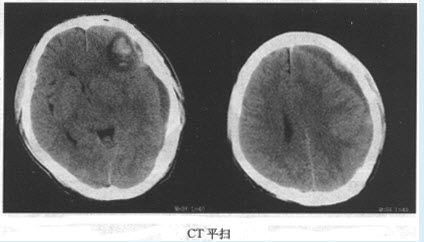

患者,男,58岁。突然剧烈头痛呕吐并摔倒3小时就诊。体格检查:患者面色苍白,全身冷汗,意识清楚,BP150/90mmHg。 患者所做CT检查如图,你诊断为何种疾病()

A:脑实质出血

B:硬膜下血肿

C:硬膜外血肿

D:蛛网膜下腔出血

E:脑挫裂伤

F:多发性硬化